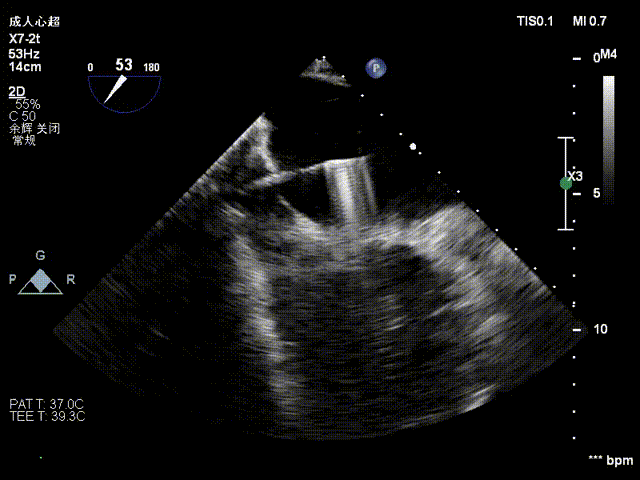

术前影像

二尖瓣后瓣腱索断裂并脱垂及关闭不全(重度)